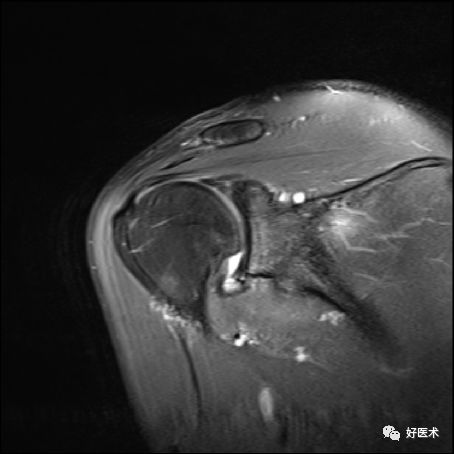

冈上肌完全撕裂

冈上肌全层撕裂伴肩撞(骨赘形成)

冈上肌全层撕裂MRI间接关节造影表现

冈上下肌撕裂